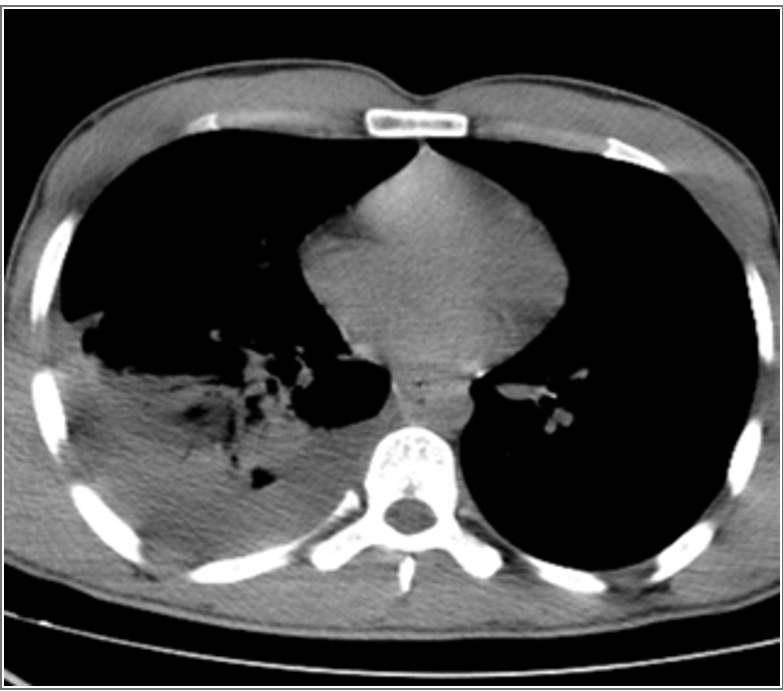

The most common symptoms in both groups were fever, cough, chest pain, and shortness of breath. All patients were diagnosed by chest X-ray and mostly by computed tomography (CT) of the thorax.

All patients had air trapping and, fluids could not be obtained by thoracentesis or with catheter/tube thoracostomy (Figure 1, 2). Consequently, all patients underwent posterolateral thoracotomy.

Figure 2. Computed tomography of the thorax of a patient with empyema